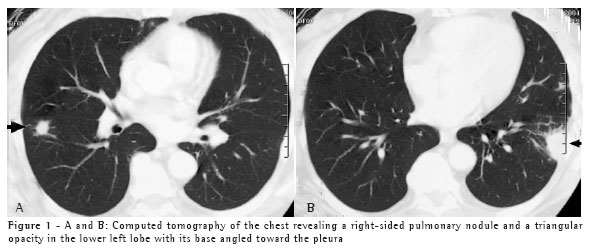

A 67-year-old white male, resident of the city of Blumenau, in the state of Santa Catarina, and a sales representative, presented with dyspnea, asthenia, chest pain, and sweats ten days after having cleaned his attic, where there are water tanks. He was in contact with bat guano for a limited period of time when the area was being swept. The presence of pulmonary nodules on the chest X-ray and tomography of the chest (Figures 1A and 1B), together with the absence of expectoration, justified the performance of a biopsy to evaluate the pulmonary nodule.